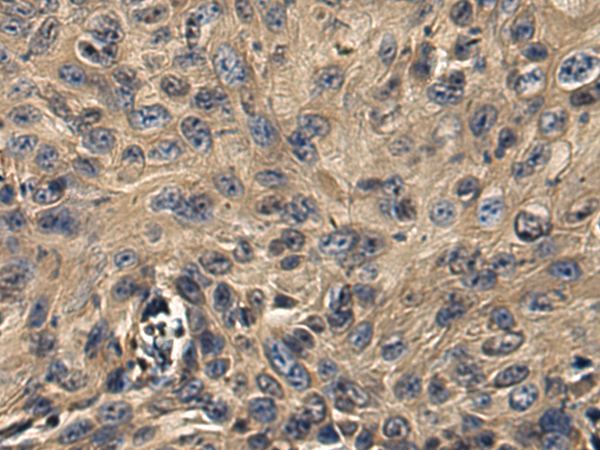

分类: 科研抗体货号: P09110别名: RCDG1应用: IHC反应种属: Human